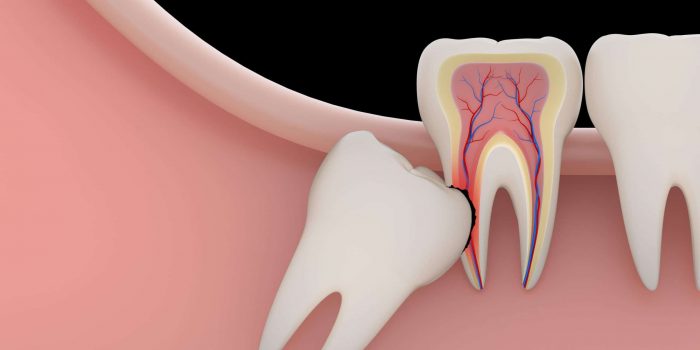

Wisdom Tooth Removal Houston

If you consider wisdom teeth removal, Epic Dental Center is the place to go. At Epic Dental Center, our team of experienced dentists can provide wisdom teeth removal services that are safe and effective. We use the latest technology and equipment to ensure that our patients receive the best possible care. Please schedule a consultation with our Wisdom Tooth Removal Dentist in Houston. We’ll be happy to answer any of your questions and help you make the best decision for your oral health. Epic Dental Center is a modern dental clinic located at 8800 Katy Fwy # 280, Houston, TX 77024. To book an appointment with us, you can visit our website or call us at (713) 365-9904.